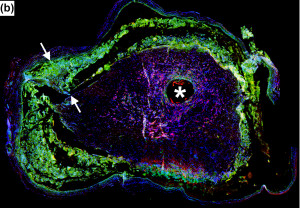

Using histological and immunocytochemical analyses, good biocompatibility of the magnesium implants was observed, with good development of regenerating nerve mini-fascicles and only mild inflammation in tissues even after complete degradation of the magnesium.

Figures A-D: Immunostained regenerating tissues after 6 weeks; (a and b) mid-conduit sections were stained for GLUT1 (green)/S100 (red)/DAPI (blue) in (a) NoMgSa and (b) MgSa animals (*cavity left by Mg, arrows delineate conduit material, bar=300μm). (c and d) Regenerating nerve mini-fascicles, indicated by arrows, run close to the Mg cavities, which are marked by * and arrowheads. The same staining was done on the section in (c), while the section in (d) was stained with ED1 (green)/NF200 (red)/DAPI (blue). Note GLUT1þ perineurium in (c) and thin layer of ED1+ macrophages above arrowheads in (d) (bar in c and d=50μm).

NoMgSa: saline filler only; MgSa: saline and Mg; GLUT1: glucose transporter 1; DAPI: 4’ 6-diamidino-2-phenylindole.2

Reproduced by permission of SAGE Publications Ltd., London, Los Angeles, New Delhi, Singapore and Washington DC.